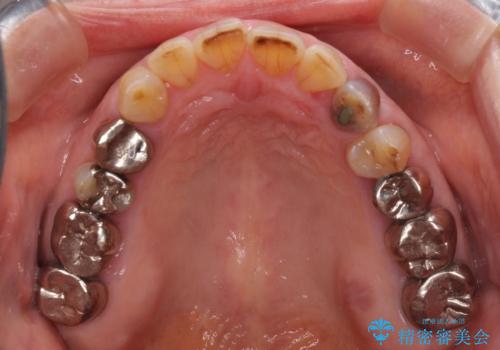

全ての奥歯の銀歯をセラミックに メタルフリー治療

- 奥歯に装着されている銀歯を全て外したいとのことで来院された患者様です。

土台に含まれている金属も含め、奥歯の金属は全て除去し、オールセラミッククラウンやセラミックインレーにて治療することとしました。